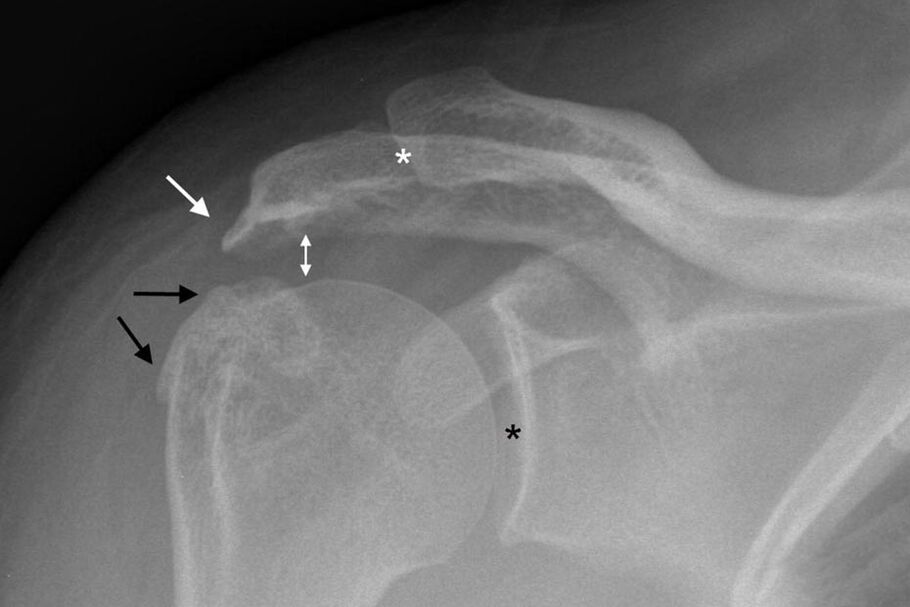

A osteoartrite da articulação do ombro pode ser diagnosticada através de uma radiografia padrão do ombro. A foto é tirada em duas projeções. O médico diagnostica a doença na presença de fatores como:

- Estreitamento do espaço articular;

- Formação de osteófitos;

- Esclerose do tecido ósseo.

Sob certas condições, outros métodos de estudo do ombro são prescritos. Ultrassom para determinar a espessura da cartilagem e avaliar a condição dos tecidos moles.

No segundo estágio do desenvolvimento da patologia, é prescrito um procedimento de artroscopia. Este é um método de pesquisa invasivo. Durante este procedimento, um endoscópio é inserido na cavidade do ombro. Simultaneamente ao estudo do estado dos tecidos, os crescimentos ósseos são removidos.

Se possível, o ultrassom e os raios X podem ser substituídos pela ressonância magnética. Este é um método informativo único de exame do corpo com artrose. O procedimento permite avaliar o estado da estrutura óssea, cartilagem e ligamentos, além de entender como tratar a artrose do ombro.